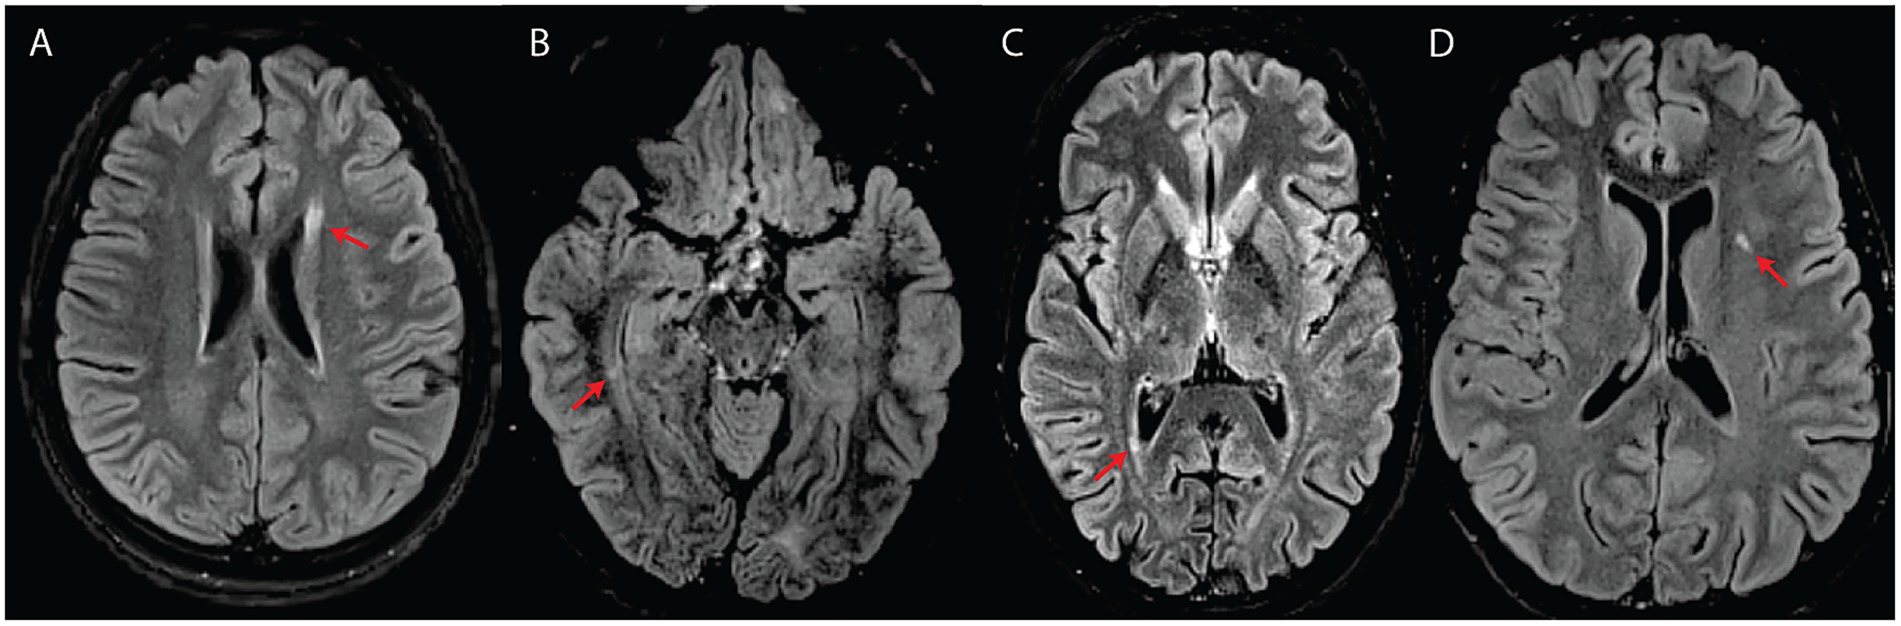

We detected T2-hyperintense white matter foci that were MS plaque-like (27–29) in seven subjects (n = 7/17; 41%) (Figures 2, 3). In four of these subjects (n = 4/17; 24%), the McDonald radiological criteria of dissemination in space and time were either fully (n = 3) or partially (n = 1) fulfilled, inciting consideration of a WFS-MS double diagnosis (Figure 2) (27). Some lesions in three of these four subjects showed gadolinium enhancement on T1-weighted imaging (Figure 2A), further supporting the existence of an underlying inflammatory process. Positive oligoclonal band status strongly supported a secondary diagnosis of MS (satisfaction of the full McDonald criteria, radiological and clinical) in the only two subjects for whom lumbar puncture was performed (#2 and #3). In both cases, a secondary diagnosis of MS was therefore communicated due to the presence of accompanying acute focal clinical deficits. MS treatment with teriflunomide was initiated in subject #3. Follow-up MRI after teriflunomide initiation documented stabilization of the multifocal white matter lesion load with worsening of pre-existing cerebellar atrophy and diffuse bilateral subcortical white matter involvement (Figures 2G–I). The observed locations and characteristics of MS-like focal lesions are summarized in Table 2.

Figure 2

Patients with fulfilled or partially fulfilled McDonald criteria. (A–C) Represent subject #2 (criteria fulfilled). (A) Axial T2-FLAIR image showing multifocal periventricular, callosal, and subcortical white matter lesions (arrows) with accompanying diffuse abnormal peritrigonal white matter signal (circle). (B) Post-gadolinium axial T1 image showing an enhancing callosal lesion. (C) Sagittal T2 image of the cervical and thoracic spinal cord showing a demyelinating lesion at the level of C3. (D–F) Represent subject #1 (criteria partially fulfilled). (D) Axial T2-FLAIR showing an oval-shaped lesion in the left temporal subcortical white matter. (E) Axial T2-FLAIR showing a periventricular lesion around the frontal horn of the right lateral ventricle. (F) Axial T2-FLAIR, performed 7 years after the first exam (D,E), showing new focal white matter lesions in the right insula, right periventricular white matter, and along the posterior horn of the right lateral ventricle. (G–I) Represent subject #3 (criteria fulfilled). (G) Sagittal T2-FLAIR showing multifocal white matter lesions perpendicular to the ventricular walls. (H) Sagittal T2-FLAIR, performed 4 years after initial MRI (G), demonstrating progression of the lesion burden in both the supra and infratentorial regions despite treatment with teriflunomide as of the first year in the 4-year interval. (I) Axial T2 spinal cord MRI showing a white matter lesion located in the left posterior cord at the C3 level.

In line with the hypothesis that some subjects in our study may be concomitantly suffering from WFS and MS, subject #3 responded to teriflunomide (Figures 2G–I). This was the only subject in our series who had started disease-modifying therapy for MS. While there is a possibility that the treatment had no impact on the natural course of WFS in this subject, it is plausible that underlying degenerative processes may have been exacerbated while inflammation was being suppressed. Even though the exact mechanisms contributing to this subject’s outcome remain undefined, simultaneous Wolframin/WFS1 deficiency and teriflunomide treatment might have imposed a significant mitochondrial stressor. Indeed, Wolframin/WFS1 plays an indirect, yet essential role in multiple facets of mitochondrial quality control putatively through modulation of Ca2+ homeostasis, while the mechanism of action of teriflunomide is the inhibition of dihydroorotate dehydrogenase, whose activity is intrinsically linked to the mitochondrial respiratory chain (19, 33). Thus, the classic WFS-associated neuroradiological features in this subject might have progressed, at least in part, because of a compounded mitochondrial insult, although dedicated studies are needed to validate this speculation.